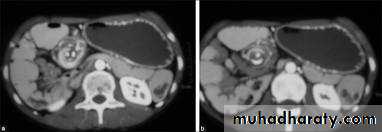

Acquired renal cystic disease (ARCD)

ARCD is cystic degenerative disease of the kidney with greater than 5 cysts visualized on CT scan. By definition, this is an acquired condition, in contrast to adult polycystic kidney disease (ADPKD), which is inherited (in an autosomal dominant fashion). It is predominantly associated with chronic and end-stage renal failure (originally, it was thought to specifically affect patients on hemodialysis).It is clinically important because it may cause pain or hematuria and is associated with the development of benign and malignant renal tumors.

Approximately one-third of patients develop ARCD after 3 years of dialysis. The male-to-female ratio is 2:1.